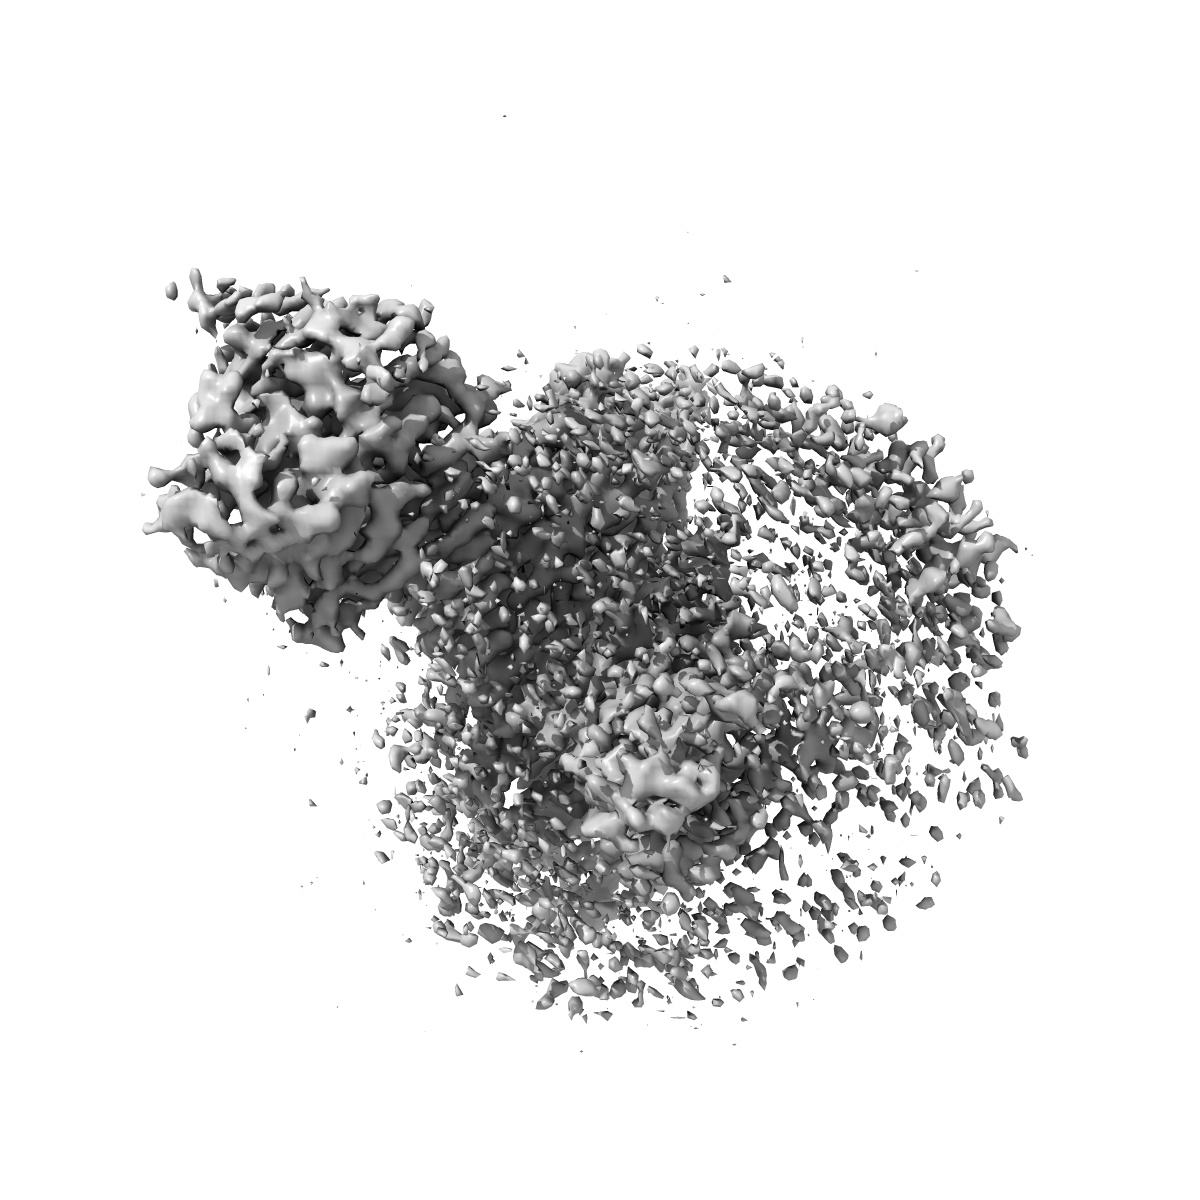

cryo-EM of human Glucagon-like peptide 1 receptor GLP-1R in apo form

Single-particle3.2 Å

Sample: cryo-EM of apo form human Glucagon-like peptide 1 receptor GLP-1R, trimeric G protein complex and stabilizing antibodies